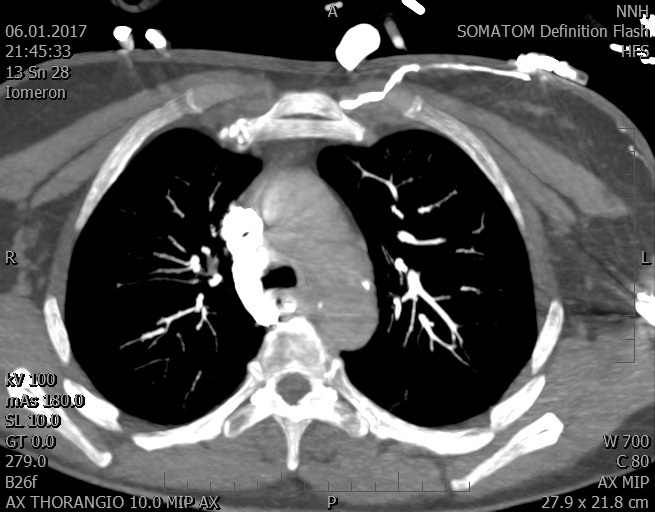

Video 1 - Akutní koronarografie prokázala normální nález na věnčitých tepnách s výjimkou suspekce na lehký spasmus na pravé koronární tepně.Echokardiograficky byla zjištěna těžká dysfunkce dilatované levé komory s nezvětšenou pravou komorou (video 2).

Video 2 - Echokardiograficky byla zjištěna těžká dysfunkce dilatační levé komory s nezvětšenou pravou komorou.Pro nejasnou příčinu zástavy jsme provedli i vyšetření výpočetní tomografií (CT), které vyloučilo plicní embolizaci (série 1 - soubory na konci článku). V den přijetí při přetrvávající oběhové nestabilitě byla nemocná opakovaně defibrilována pro fibrilaci komor se stabilizací rytmu po podání amiodaronu a mesocainu. Dle hemodynamických měření se jednalo o těžký kombinovaný šok. Vstupní laboratorní vyšetření bylo bez větších pozoruhodností. Posléze jsme doplnili anamnézu od příbuzných a zjistili, že pacientka užila do dvou hodin před srdeční zástavou první tabletu amoxicilinu na lehký respirační infekt. Při nevýtěžnosti vstupních vyšetření a nových anamnestických informacích jsme doplnili 14 hodin po kolapsu vyšetření koncentrace tryptázy v séru, která byla extrémně zvýšena (tabulka 2), což nás vedlo k podezření na anafylaxi.